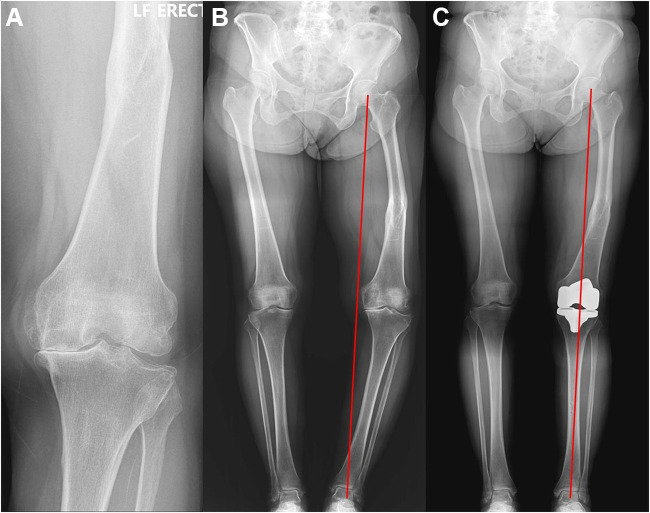

背景:在股骨或胫骨创伤后关节外畸形的情况下,实现适当的轴对齐可能是困难的。我们介绍了机器人辅助全膝关节置换术(TKA)对伴有创伤后关节外畸形的膝关节骨性关节炎患者的放射学结果。方法:我们分析了5例患者(1)Kellgren-Lawrence (K-L) III-IV级骨关节炎膝关节,(2)股骨或胫骨存在创伤后关节外畸形,(3)接受机器人辅助TKA的患者的5个膝关节的结局。对他们的放射学表现进行了评估。结果:所有初始畸形的5个膝关节(平均14.8°,范围12.7-18.5°)均被矫正为中立位(平均0.7°,范围-1.1-2.7°)。术后髋关节-膝关节-踝关节(HKA)角度无异常值。结论:我们的研究结果表明,机器人辅助的TKA可以用于创伤后关节外畸形患者实现正确的肢体对准。

Methods: We analyzed the outcomes of five knees in five patients with (1) Kellgren-Lawrence (K-L) Grade III-IV osteoarthritic knees, (2) the presence of posttraumatic extra-articular deformities either in the femur or the tibia, and (3) who underwent robot-assisted TKA. Their radiological findings were evaluated.

Results: All five knees with initial deformity (mean 14.8°, range 12.7-18.5°) were corrected to neutral alignment (mean 0.7°, range -1.1-2.7°). There was no postoperative outlier of hip-knee-ankle (HKA) angle.